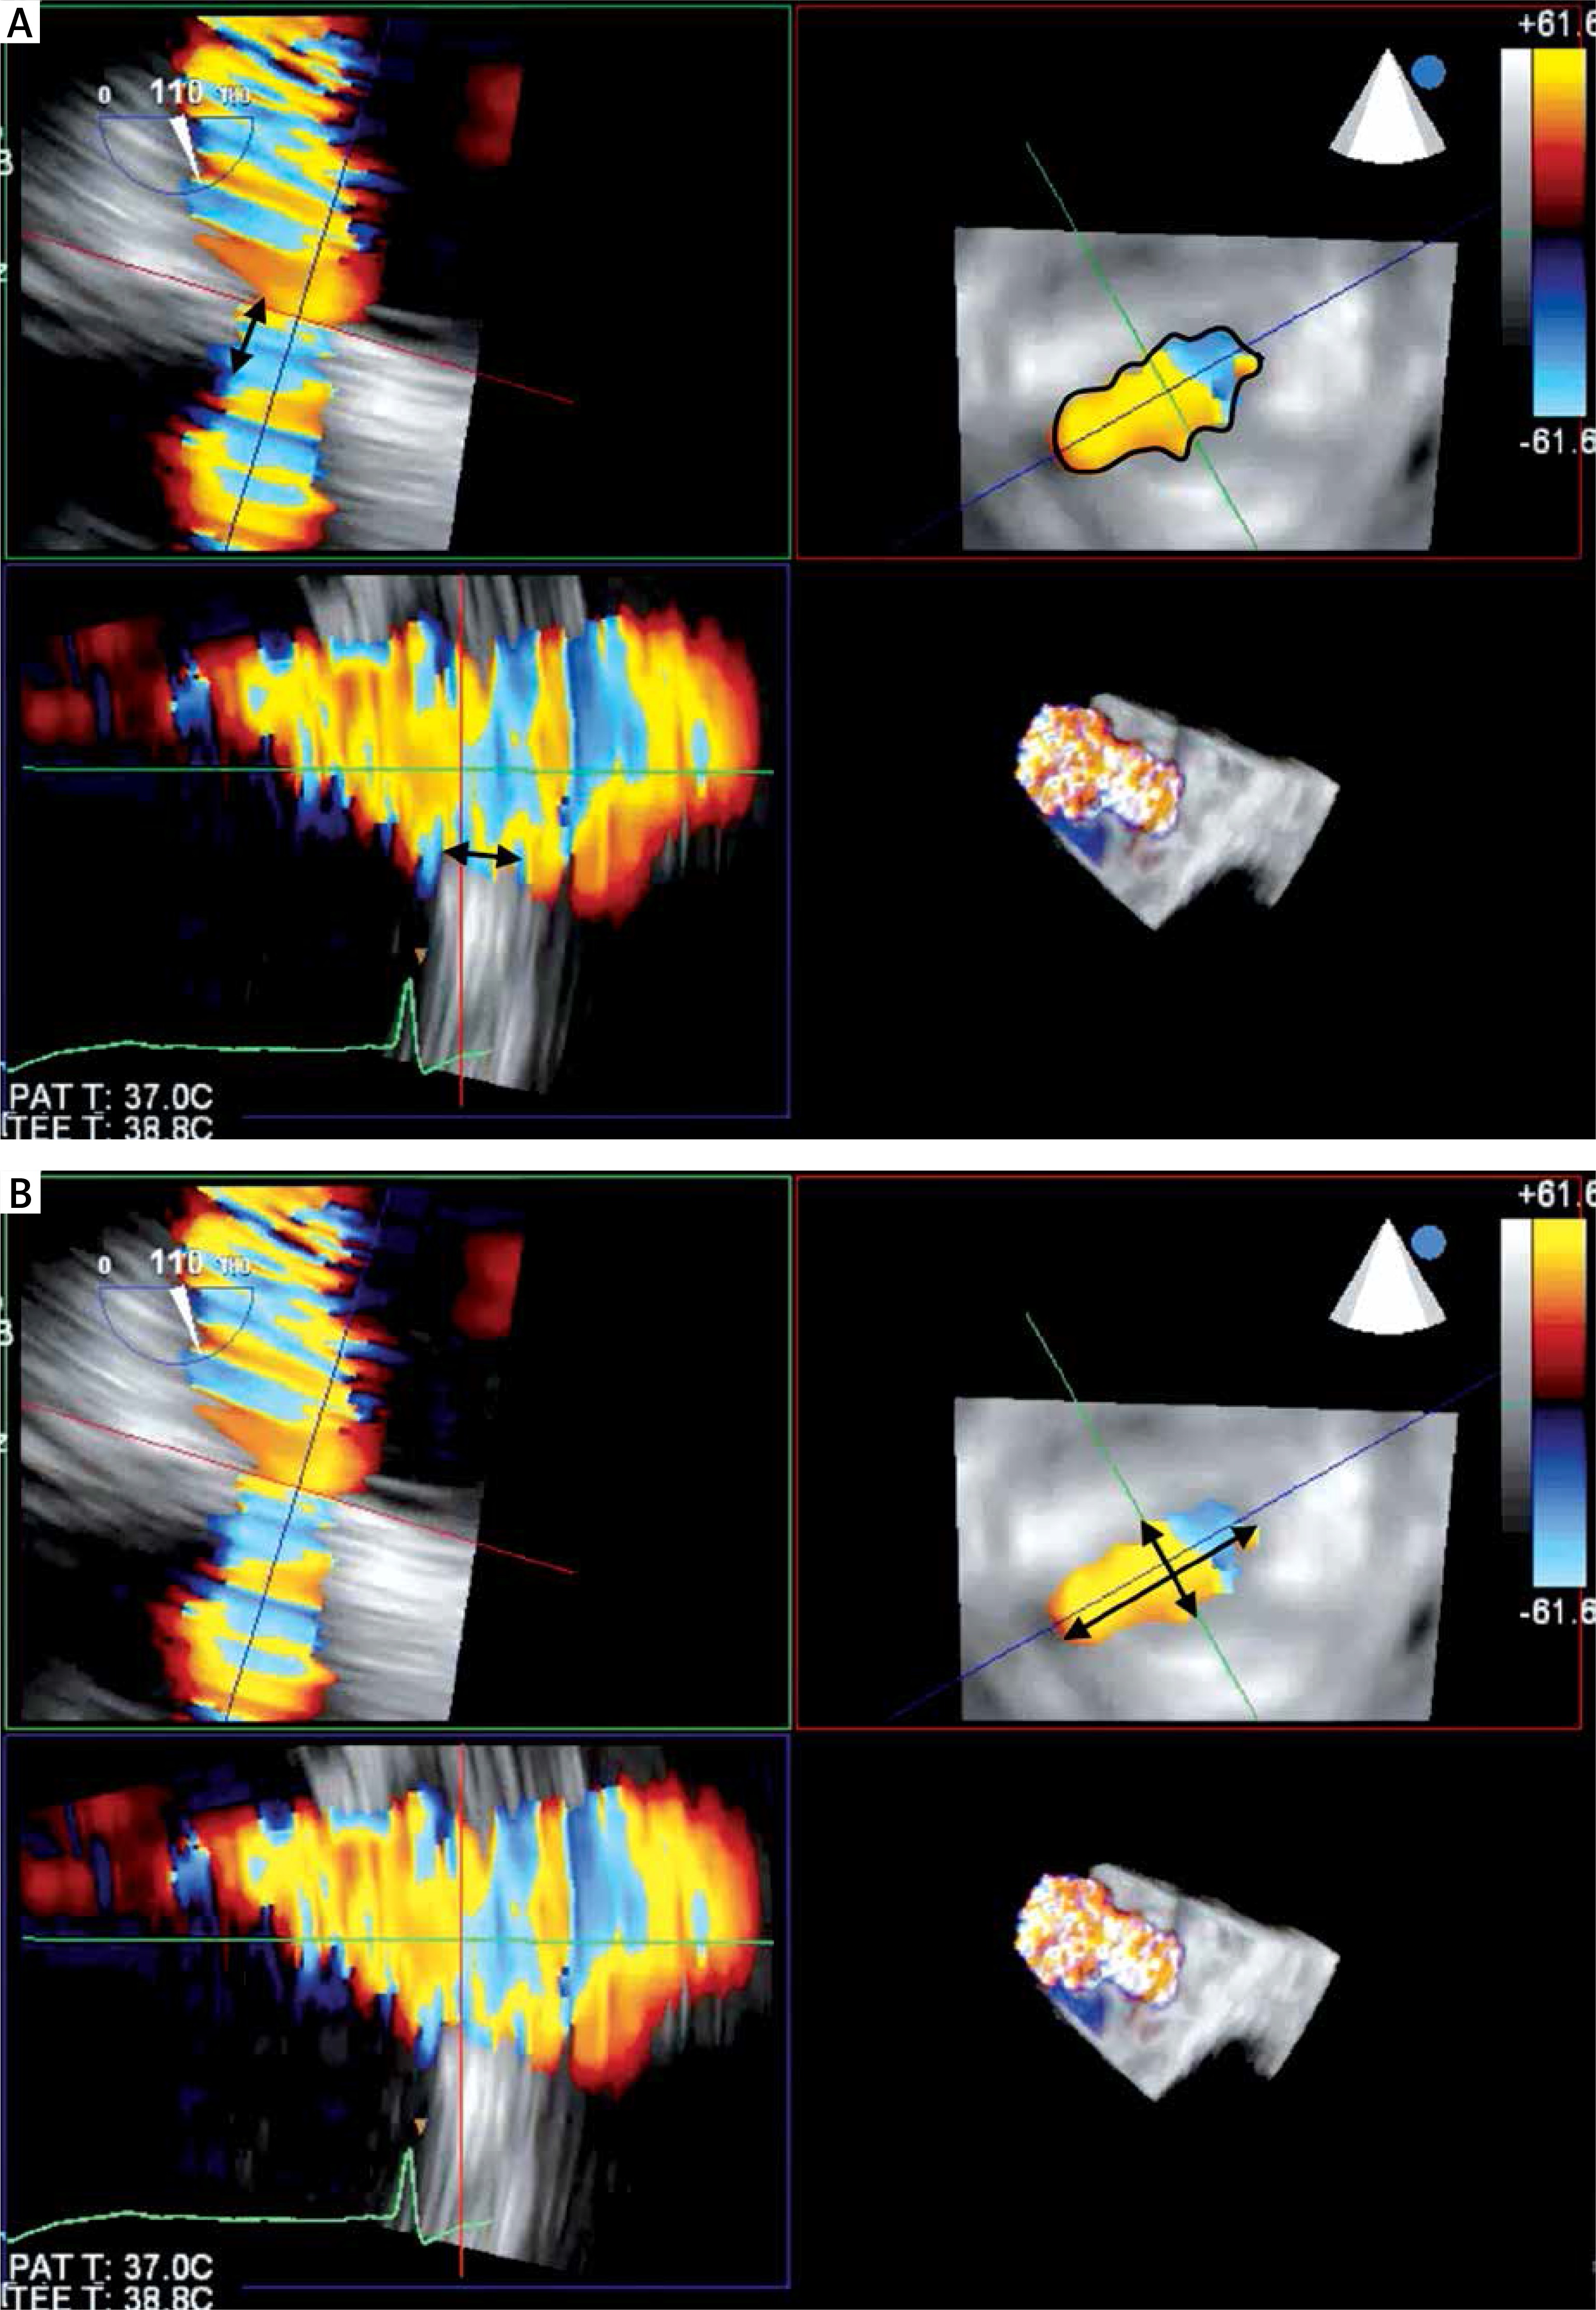

To ensure optimal spatial and temporal resolution, we acquire the smallest possible volumes containing the complete PVL channel in an ECG-gated, single-beat zoom 3D High Volume Rate (HVR) mode with color doppler (CD). Such visualization of PVL opacification by CD-mapped flow turbulence is used for detailed PVL anatomy analysis. With acquired volume being replayed in the multiplanar presentation the PVL channel is reoriented within the three perpendicular planes until two of them are positioned parallel to the flow direction while the third one is perpendicular and at the level of the vena contracta (VC) – Figure 1. Pivotal for the device choice are the cross-sectional area (CSA) and the minimum (width – W) and maximum (length – L) diameters of VC, all measured on the image frozen at the time of maximum paravalvular backflow. Analogously, the channel depth, understood as the distance between cavities of the left ventricle (LV) and left atrium (LA), can be verified (Figures 2 A and B). The size and number of plugs are chosen in previously described manners according to either CSA for AVP III [9, 11] or W and L for PLD [12].

A – Fluoroscopy image of a properly expanded PLD (PLD closing mitral PVL, arrows pointing at the discs of PLD). B – Fluoroscopy image of a deformed PLD (arrows pointing at the discs of PLD)

MV – mitral prosthetic valve, AV – aortic prosthetic valve.